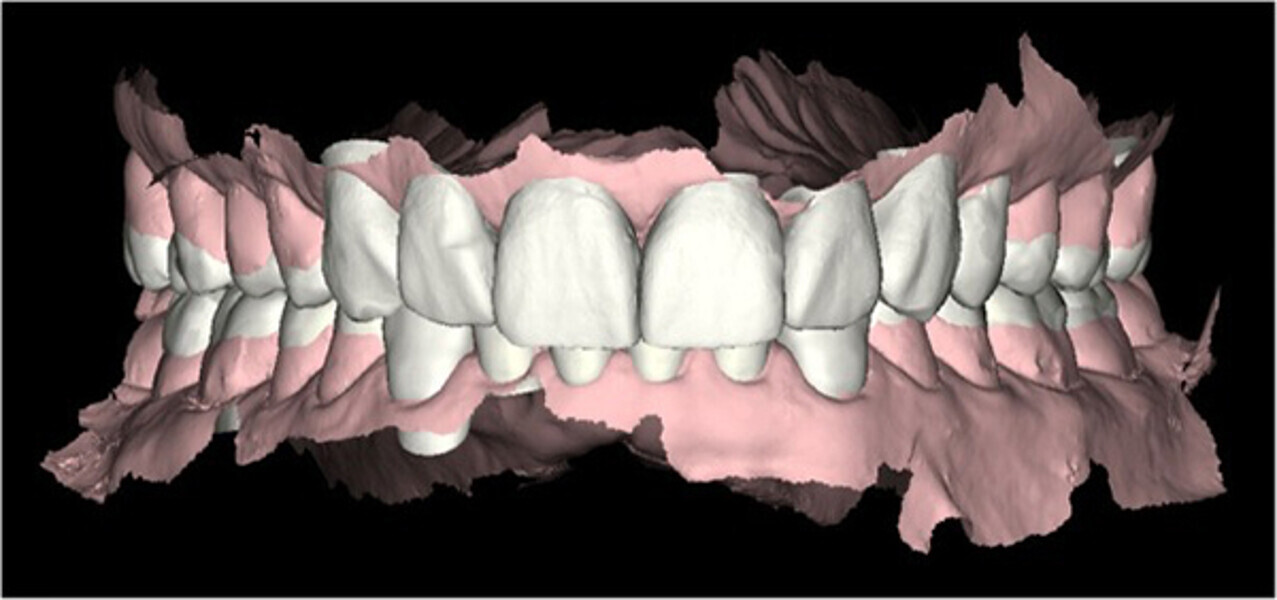

Fig. 3. Escaneado intraoral inicial con Carestream 3500.